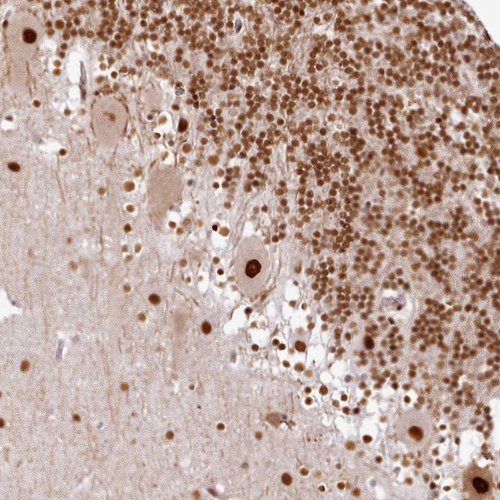

Immunohistochemical staining of human cerebellum shows strong nuclear positivity in Purkinje cells.